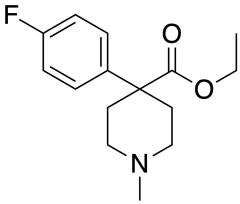

4-Phenylpiperidines

Pethidines (meperidines)

- 4-Fluoropethidine

- Allylnorpethidine

- Anileridine

- Benzethidine

- Carperidine

- Difenoxin

- Diphenoxylate

- Etoxeridine (carbetidine)

- Furethidine

- Hydroxypethidine (bemidone)

- Morpheridine

- Meperidine-N-oxide

- Oxpheneridine (carbamethidine)

- Pethidine (meperidine)

Structures